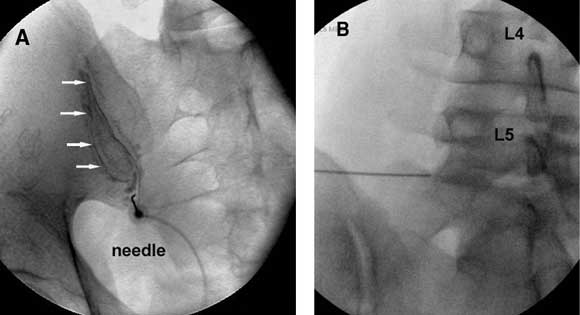

Joint blocks Joints thought to be the source of pain can be anaesthetised by injecting local anaesthetic into the joint (Figure A) or by blocking the nerves that supply the joint (Figure B). |

A: Oblique anteroposterior radiograph of a sacroiliac arthrogram. A needle has been inserted into the cavity of the sacroiliac joint and contrast medium (arrows) injected to confirm intra-articular placement, before injection of local anaesthetic (image kindly provided by Dr Paul Dreyfuss, Seattle, Washington). B: Anteroposterior radiograph showing a needle in place for a left L5 medial branch block. |